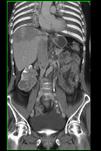

问题 男,53岁,体重明显下降而行CT检查,如图所示,下列说法正确的是 ( )

选项 A、此为右侧肾癌 B、癌栓侵入下腔静脉并扩散至右心房 C、肾平面以上的下腔静脉内均有软组织密度影 D、右心房内可见充盈缺损 E、右肾区可见不规则的软组织块,增强为不均匀强化

答案 ABCDE